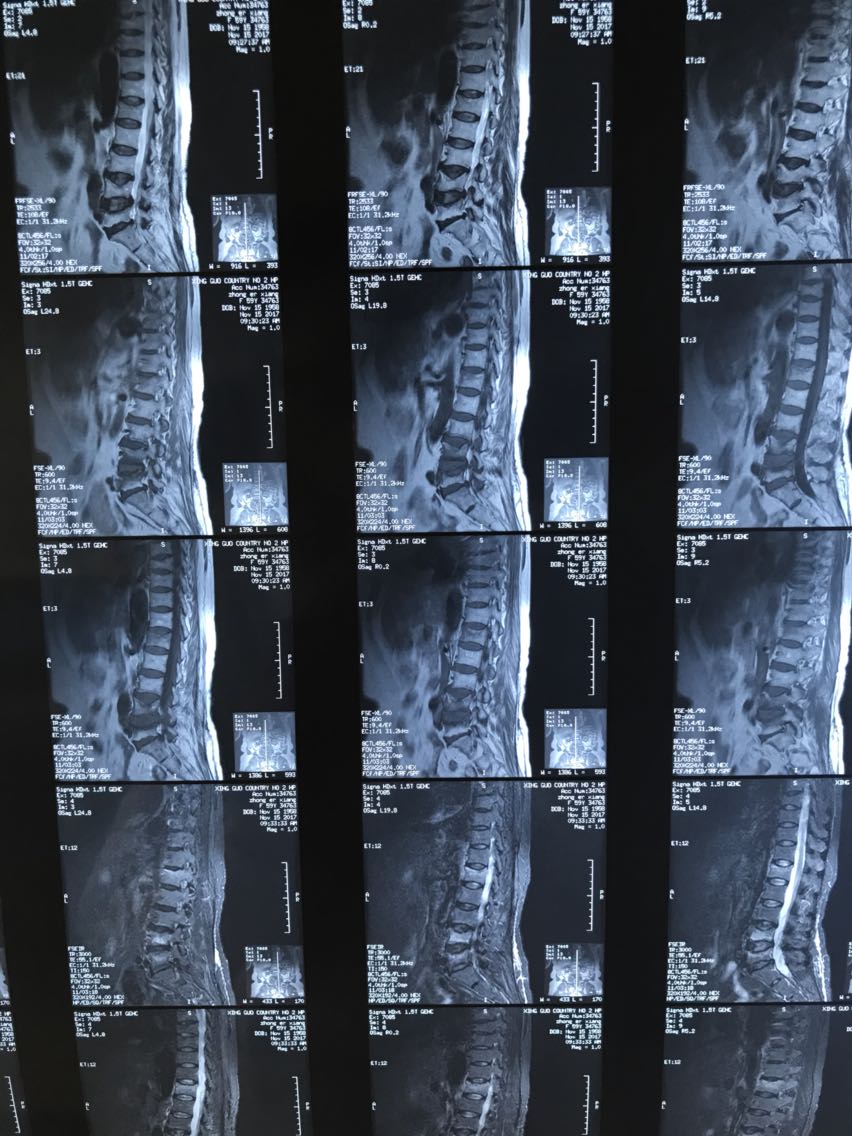

病理性骨折需要手术吗

病理性骨折